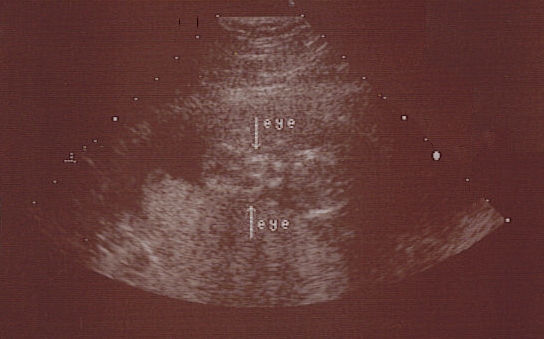

Last night Pablo and I had to run to Labor and Delivery at the hospital for some tests due to some unexpected (and slightly profuse) bleeding. All tests checked out normal, and Rory is fine (no placental abruption or anything like that), although the med staff couldn't tell us what would have caused the bleeding, so we're left answer-less. We did get a new ultrasound photo, though, so take a look. She's due in exactly 2 months (but measuring big, so maybe she'll come a little early? I've still only gained 5 lbs since November (yay!) so I'm feeling pretty good, all things considered.

This is the same Ultrasound partially colorized to help you see her better

hips <---------------------------> head

looking stright toward you